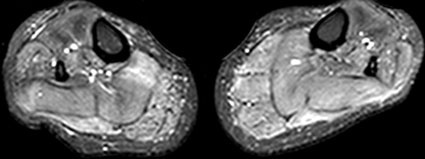

Vergleichen Sie die Unterschenkel in (B) mit deutlichen ödematösen Veränderungen in der Unterschenkelmuskulatur bds. auf den STIR-Bildern bei einer 37-jährigen Frau mit Hypokaliämischer Periodischer Paralyse Typ-1 (C), bei der pathophysiologisch eine Wassereinlagerung und eine exzessive Na+-Akkumulation in den Muskelzellen vorliegt.